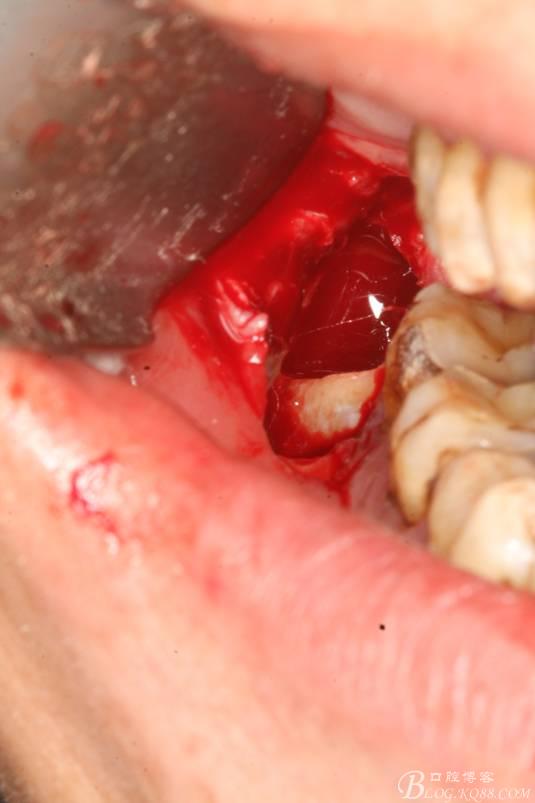

7.取出牙冠

8.清理拔牙創(chuàng)